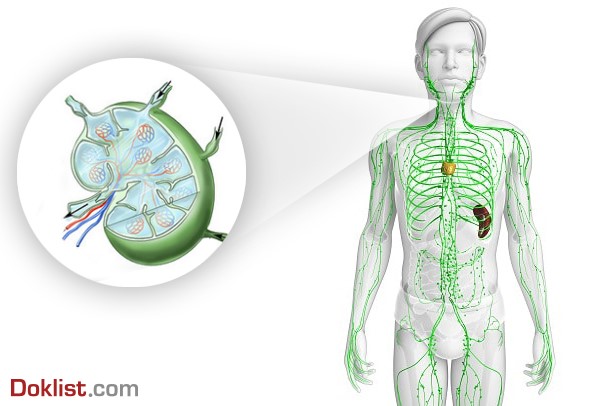

Em resumo, anatomicamente, o sistema linfático é uma rede de órgãos linfoides, linfonodos, ductos linfáticos, tecidos linfáticos, capilares linfáticos e vasos linfáticos.

Estrutura do Sistema Linfático com ênfase ampliada do Linfonodo.

Como vimos no resumo da semana passada, as células dendríticas (DCs) são especializadas na captura e apresentação de antígenos para os linfócitos, e por sua vez, são consideradas uma ponte entre a imunidade inata e a adaptativa, justamente por serem atraídas e ativadas por elementos da resposta inata e viabilizarem a sensibilização de Linfócitos T da resposta imune adaptativa.

Essas, residem em tecidos periféricos, como pele, fígado e intestino, onde capturam antígenos e se tornam ativadas. Após isso, tais células serão direcionadas e migrarão diretamente para os linfonodos regionais, que são responsáveis por processar e apresentar antígenos proteicos ou lipídicos aos LTs (5, 7).

Sabe-se que DCs imaturas são altamente eficientes na captura de antígenos, enquanto as maduras são muito eficientes na apresentação.Os antígenos capturados são processados dentro da célula e apresentados em sua superfície, inseridos em moléculas do MHC. Em geral, antígenos proteicos são apresentados por moléculas MHCs clássicas, de classes I e II (5, 7)